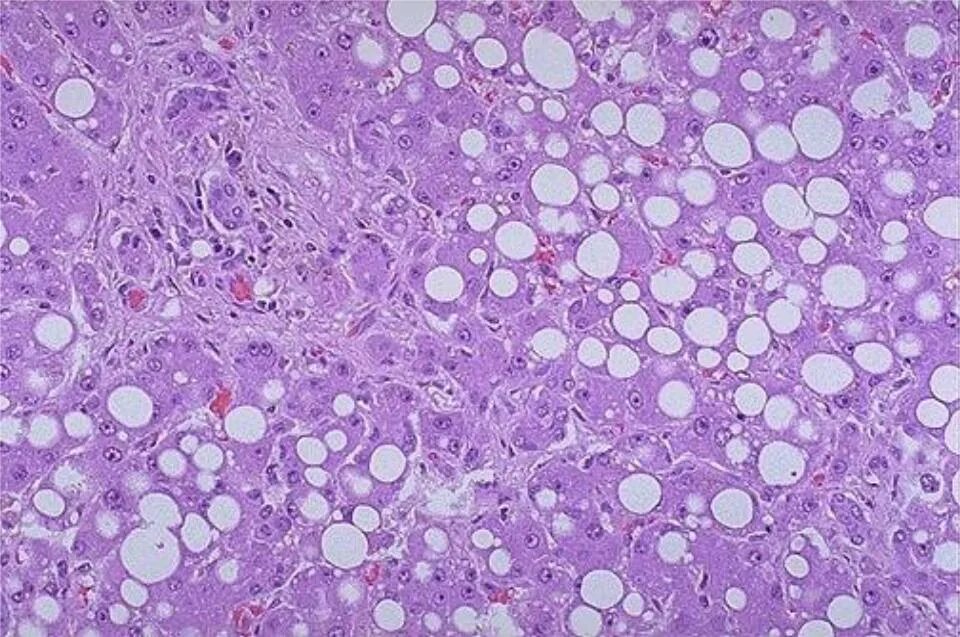

Липидоз печени